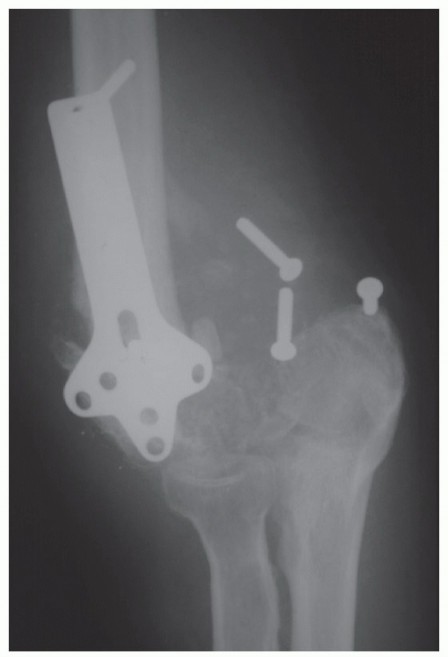

DEFINITION Radial head fractures are the most common fracture of the elbow and usually can be managed either …